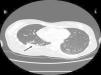

Case reportA female patient with a congenital muscular dystrophy had been treated with nocturnal nasal noninvasive positive pressure ventilation (NIV) since she was 20. At the age of 26 she was hospitalised for a complete atelectasis of the right lower lobe, and had recovered after more than a month with the application of an intensive combined protocol of HFCWO (The Vest Airway Clearance System, Hill-Rom St. Paul, MN, USA) plus manual and mechanical assist cough (In-Exsufflator, Cough-Assist®, Philips Respironics, Murrysville, PA, USA). Her clinical condition remained good until the age of 28, when her lung function tests showed the following values: vital capacity 0.55 L (16% of the predicted value), maximal inspiratory pressure 10cmH2O (11% of predicted), maximal expiratory pressure 14cmH2O (13% of predicted), and peak cough expiratory flow 80L/min. A few months later, due to the appearance of fever and copious mucus production, she was treated with manual and mechanical chest physiotherapy plus antibiotics (ceftriaxone) initially. However, she still complained of dyspnea and a feeling of retained secretions, and was then admitted to hospital. She had a severe left convex scoliosis with a mean Cobb angle of over 70°. After a chest X-ray, a CT scan was performed (Fig. 1) which showed atelectasis of the right lower lobe. Her diurnal arterial oxygen saturation (SpO2) fluctuated between 82 and 85% in room air, while PaCO2 was normal. The patients showed minimal clinical signs of dehydration, namely dry mouth. She had good skin turgor and normal urine output. Haematocrit and electrolytes were normal except for potassium which was lower than normal. We began nutritional support and hydration because the patient was not able to eat and drink enough. Negative results were obtained from sputum cultures; however, intravenous antibiotics were administered. Twenty-four-hour NIV was begun, with the addition of oxygen (5L/min), as NIV alone was not enough to maintain SpO2 above 90%. Fifteen-twenty minutes sessions of HFCWO at a pressure of 5cm H2O and a frequency of 12Hz were performed; each session was followed by five or six sessions of mechanical assist cough with an In-Exsufflator at pressures of +40/−45cm H2O, delivered respectively over 3 and over 2s, with an abdominal thrust timed to the exsufflation cycle. This protocol was applied 4 times/day; additionally, In-Exsufflator was used on demand. Once 24-h NIV had begun, we asked the patient to frequently change her decubitus. However, as she had a severe scoliosis, she hardly changed her body position tending to remain on her right side. As the patient demonstrated a modest clinical improvement, we hypothesized that bronchial secretions had a high concentration of DNA due to accumulation of degenerated leukocytes. Therefore, one week after admission we tested rhDNase (Pulmozyme®; Roche, Basel, Switzerland). For three days, 2.5mg were delivered twice daily with a jet nebulizer, using an in-line nebulizer with NIV, without success. The next day flexible fiberoptic bronchoscopy (FOB) was performed, during NIV plus oxygen, to get a better evaluation of the cause of the obstruction and to possibly instill rhDNase bronchoscopically. FOB showed a lot of very thick mucus in the lower right lobe, but, due to its high viscosity, only a small amount could be removed. Then, a single dose of 2.5mg rhDNase was instilled directly over the affected area. As the procedure was performed in a clinical ward and the patient was at risk of intubation, this was carried out together with an Intensivist. Anyway, we had no complications except for a mild transient decrease in SpO2. The patient was closely monitored by trained nurses. Copious but thinner secretions were removed with the help of the In-Exsufflator. It had to be used six times in the first hour and three times in the second hour for periods lasting from 1 to 2min to 10 or more consecutive minutes. In the following hours the In-Exsufflator was applied only according to the protocol and within 24h a significant clinical improvement was evident, with a reduced need of oxygen. A new CT scan demonstrated a significant reduction of the atelectatic area (Fig. 2). The treatment was repeated two days after the first instillation with the same dose of the drug, with a further clinical improvement that allowed us to withdraw oxygen. Even after the second instillation, MI-E was often required, four times in the first hour and once in the second hour, unlike in the following days when it was applied only according the protocol. Two days later the patient was discharged (Table 1). A month later the clinical and radiological recovery was confirmed (Fig. 3).